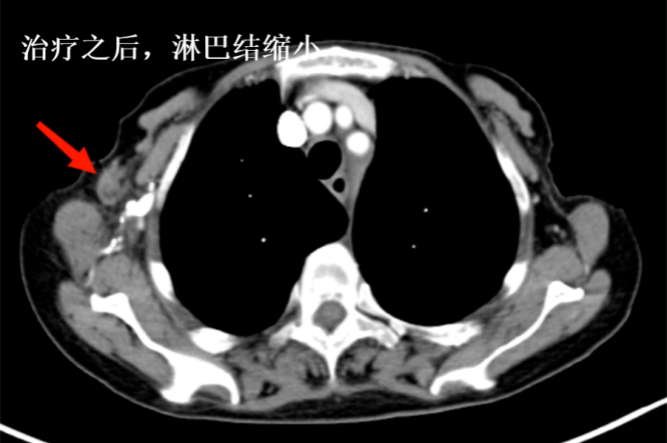

再一次復(fù)查時(shí),她的身體狀況明顯好轉(zhuǎn),體內(nèi)的腫瘤竟然再次大幅度縮小,精神面貌也煥然一新,胸悶和全身水腫的癥狀完全消失。如今,她不僅能夠完全自理生活,生活質(zhì)量與常人無(wú)異。